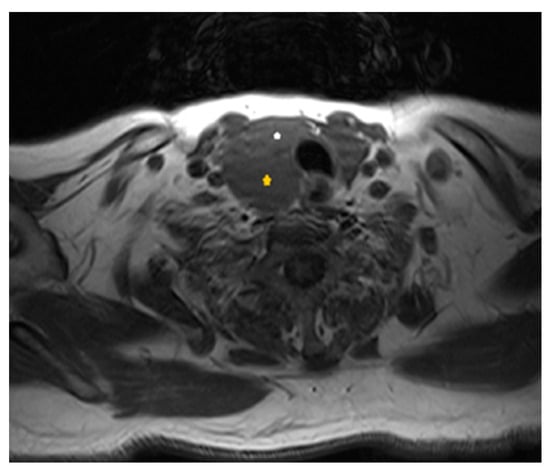

2. Case Presentation

2.1. Diagnostic Assessment

2.4. Histology